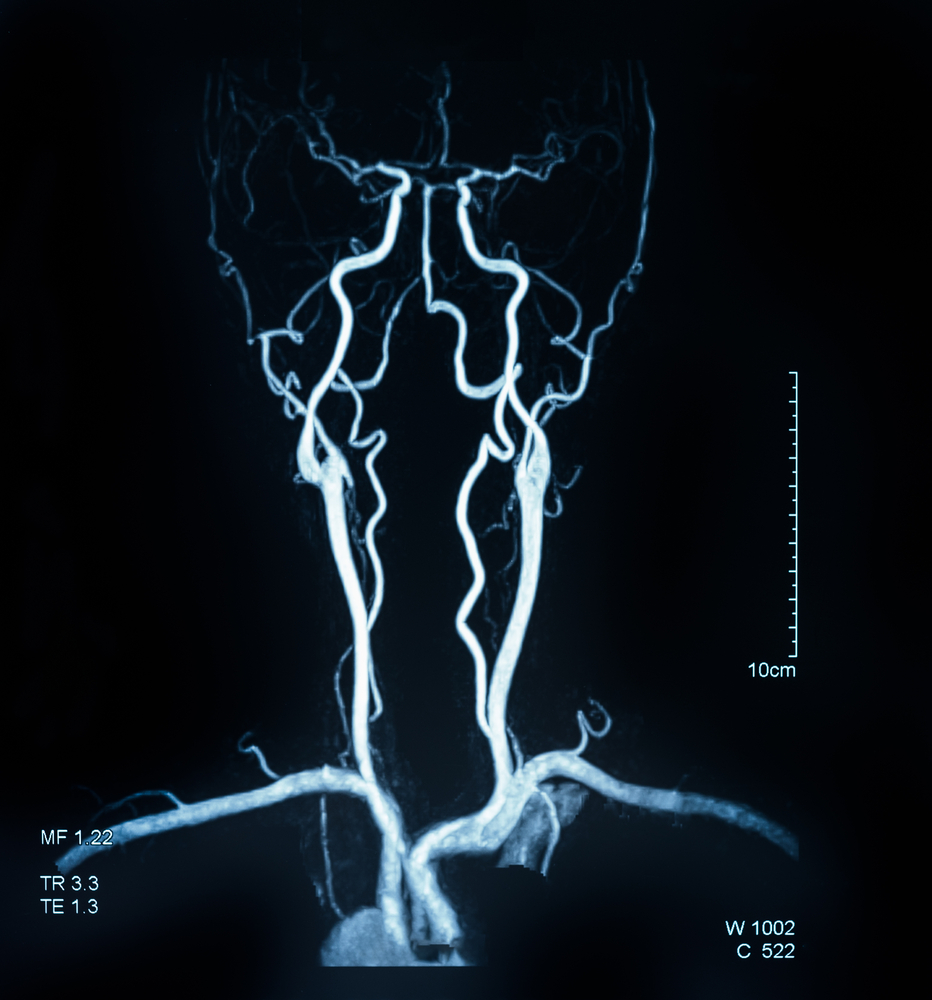

- компьютерная обработка информации позволяет получить трехмерное изображение сосудов абсолютно в любой точке исследования (это касается так называемой спиральной КТ-ангиографии, проводимой на специальном спиральном томографе);

- она проводится с помощью магнитно-резонансного томографа, то есть в основе метода лежит явление ядерно-магнитного резонанса. Это означает полное отсутствие рентгеновского излучения при процедуре (и поэтому МР-ангиография разрешена при беременности);

преимуществом перед другими видами ангиографии. При необходимости использования контраста, вещество также вводится в вену локтевого изгиба через периферический катетер; - изображение сосудов получается трехмерным благодаря компьютерной обработке;

В целом, можно сказать, что КТ и МР-ангиография являются современными, менее опасными и более информативными методами исследования, нежели обычная ангиография сосудов головного мозга. Однако они не всегда выполнимы, поэтому обычная ангиография сосудов головного мозга по-прежнему является актуальным методом исследования сосудистой патологии головного мозга.

Таким образом, ангиография сосудов головного мозга – весьма информативный метод диагностики, в основном, сосудистых заболеваний головного мозга, в том числе стенозов и окклюзий, являющихся причиной инсультов. Сам по себе метод довольно доступный, требует лишь наличия рентгеновского аппарата и контрастного вещества. При соблюдении всех условий подготовки и проведения исследования ангиография сосудов головного мозга дает точный ответ на поставленный перед нею вопрос с минимальным количеством осложнений. К тому же современная медицина располагает такими инновационными методами, как КТ и МР-ангиография, более шадящими, менее вредными и травматичными для больного. КТ и МР-ангиография позволяют получить трехмерное изображение сосудов, а значит, с большей долей вероятности, не пропустить имеющуюся патологию.